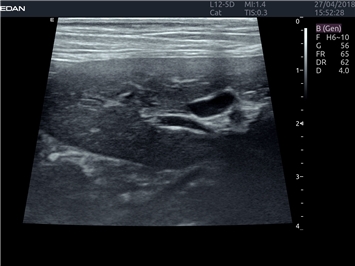

УЗИ-аппарат

EDAN Acclarix LX4 VET

Расширьте свои представления. Когда речь заходит о стабильности, производительности и эффективности, существует одна ультразвуковая система, которая расширяет возможности ветеринарных исследований.

EDAN Acclarix LX4 VET представляет собой профессиональную ультразвуковую систему, специально разработанную для ветеринарных исследований. Сочетание стабильности, высокой производительности и эффективности делает эту систему идеальным выбором для современной ветеринарной практики.